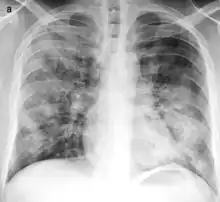

| Typical distribution of lobar pneumonia (left in image) and bronchopneumonia (right in image) | |

Bronchopneumonia is a subtype of pneumonia. It is the acute inflammation of the bronchi, accompanied by inflamed patches in the nearby lobules of the lungs.[1]

It is often contrasted with lobar pneumonia; but, in clinical practice, the types are difficult to apply, as the patterns usually overlap.[2] Bronchopneumonia (lobular) often leads to lobar pneumonia as the infection progresses. The same organism may cause one type of pneumonia in one patient, and another in a different patient.